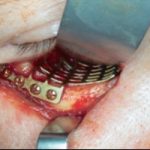

Vor der Einleitung der Analgesie, die noch ein Mitagieren des Patienten ermöglichte, wurde der Patient an das Monitoring angeschlossen. Die eingehende Untersuchung stellte ein im Unterkieferknochen links steckendes Geschoss dar, welches in Haut und Muskulatur einen ca. 5 cm großen Defekt verursacht hatte. Mehrere kleine Einsprengungen verteilt über die linke Gesichtshälfte von der Schläfe bis zum Hals (Bild 2) waren für die Primärversorgung zunächst ohne Relevanz. Nach Sicherung der Vitalfunktionen und Analgesie, wurden zwei Röntgenaufnahmen (PSA und HWS) angefertigt, die übereinstimmend eine Fraktur der Mandibula ausschlossen (Bild 1).

In der anschließenden problemlosen Intubationsnarkose erfolgte die Entfernung des Projektils durch die Eintrittswunde (Bild 3 und 4). Auftretende Blutungen konnten durch Elektrokoagulation gestillt werden. Des weiteren wurde ein Debridement der Wunde durchgeführt und die Wunde mit Kochsalz-Lösung gespült. Es erfolgte ein Wundverschluss in mehreren Schichten mit eingelegter Drainage (Bild 5).